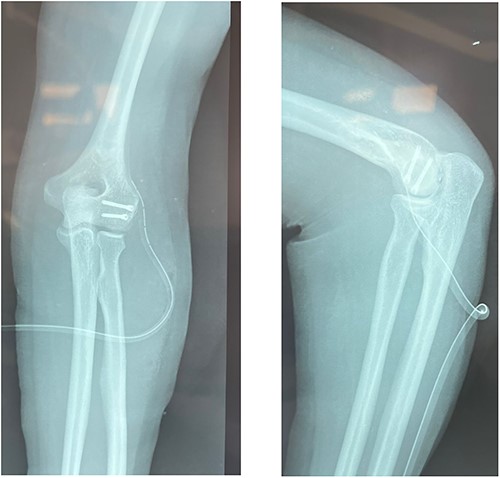

This is a prospective, monocentric study of adult patients undergoing surgical treatment for isolated capitellar fracture. Between 2019 and 2022, we received eight patients (six men and two women) with a mean age of 25 years (18–40 years) who had type I fracture of the capitellum. The dominant arm was affected in six patients (Table 1). All our patient had a fall on an outstretched hand. All fractures were close and isolated without any vascular or neurological damage. Standard AP (anteroposterior), lateral X-rays (Fig. 1) as well as a computed tomography (CT) scan with 3D reconstruction were done for all the patients (Fig. 2). Therefore, fractures with trochlea involvement were excluded.